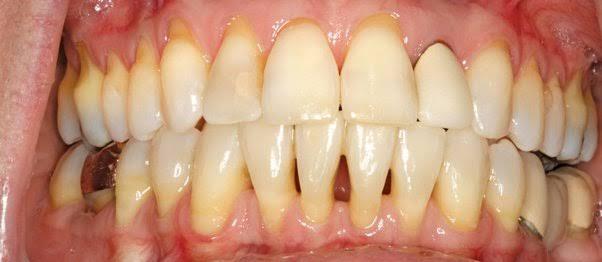

Gusi turun atau yang dalam dunia medis dikenal sebagai resesi gingiva. Resesi gingiva adalah suatu kondisi ketika gusi merosot atau turun ke bawah dari permukaan gigi sehingga memperlihatkan permukaan akar gigi yang akan mengganggu estetika. Kondisi ini tersebut merupakan salah satu gejala dari penyakit gusi (periodontitis). Resesi gingiva adalah masalah yang umum pada orang dewasa di atas usia 40 tahun. Namun, kondisi ini juga dapat terjadi pada usia remaja. Gusi turun dapat diatasi dengan mengurangi faktor risikonya.

Berbagai masalah dapat timbul akibat gusi turun, yaitu masalah estetik, karies pada permukaan akar gigi, dan gigi menjadi sensitif yang menyebabkan pasien merasa tidak nyaman. Oleh karena itu, umumnya perawatan yang dilakukan bertujuan memperbaiki estetik dan menghilangkan keluhan utama yang dirasakan pasien. Rencana perawatan sangat bervariasi tergantung dari penyebabnya.